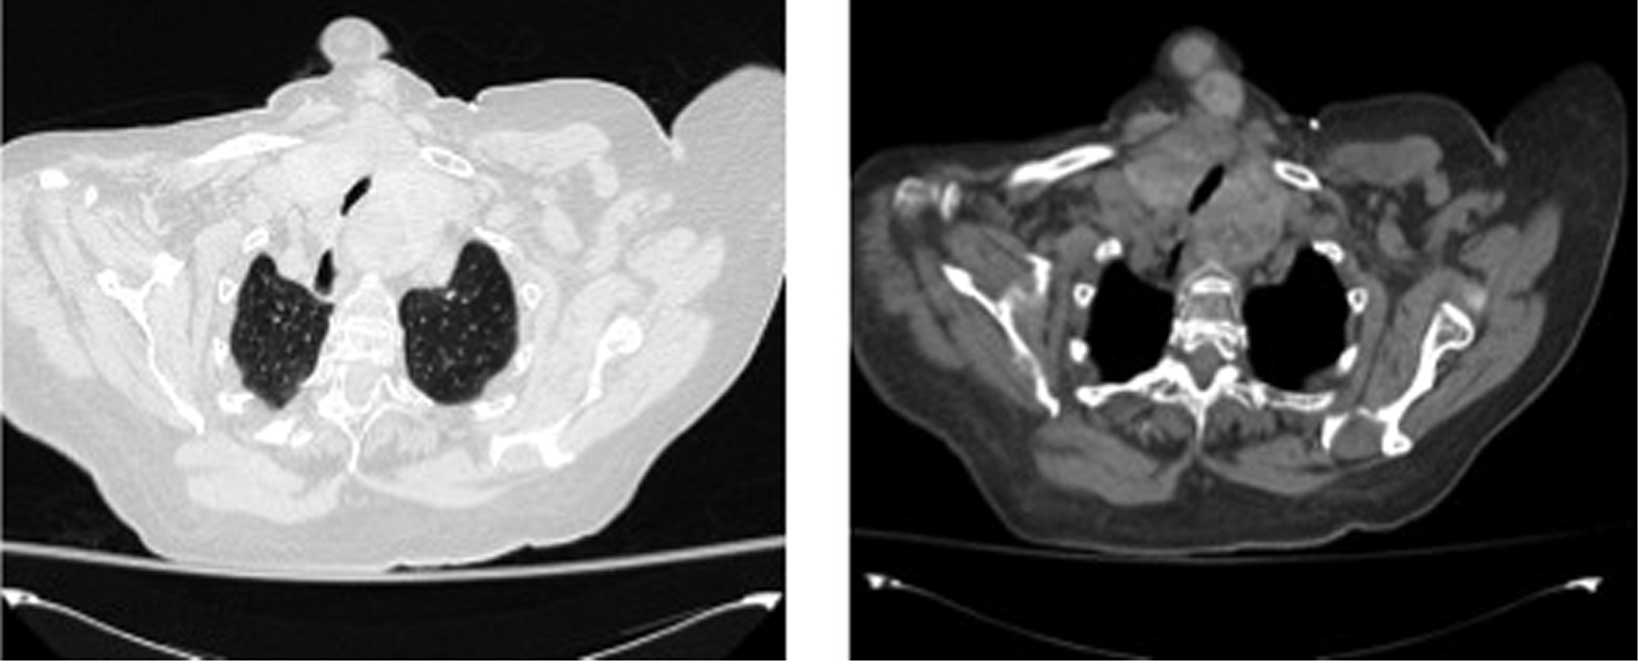

A 85-year-old female was transferred on the 14th of January, 2014 to the Department of Clinical Medicine and Rheumatology, Campus Bio-Medico University of Rome (Rome, Italy) with acute respiratory failure and pneumonia. Arterial blood gas (ABG) analysis showed the following: pH, 7.43; pO2, 54 mmHg; pCO2, 40 mmHg; and HCO3, 28 mmol/l, and pneumonia. Venous blood tests demonstrated the following: Hemoglobin (Hb), 11.6 g/dl; platelets, 166,000 cells/µl; white blood cell (WBC), 6,490 cells/µl (neutrophils, 4,860 cells/µl; lymphocytes, 860 cells/µl); and creatinine, 0.84 mg/dl. Following admission, oxygen therapy using a Venturi mask (40%) at 8 l/min and antibiotic therapy using piperacilline/tazobactam (4.5 g three times a day) were administered intravenously. The patient's medical history included several years of follow-up for a thyroid goiter; however, computed tomography (CT) analysis of the neck demonstrated a multinodular goiter in the mediastinum with severe compression of the tracheal lumen that appeared markedly reduced in size and was deformed in a way that it resembled a mouse tail (Fig. 1). In addition, a sliding gastric hiatal hernia resulted in compression of the anterior-medial part of the left inferior lobe. This induced marked dilation of the esophageal lumen with ‘air-fluid level’.

Figure 1.

Axial computed tomography with a contrast agent in the mediastinal window (right) and in the parenchymal window (left). It shows a multinodular goiter in the mediastinum with severe compression of the tracheal lumen and a marked reduction in size and deformation of the trachea is observed.